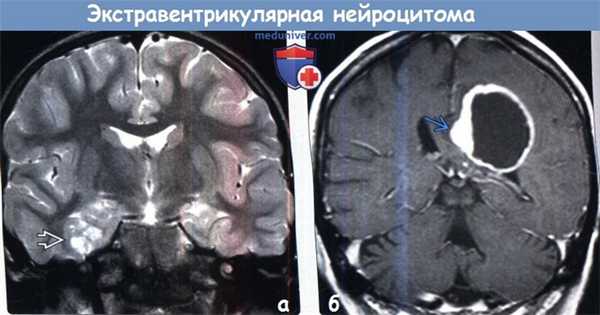

(а) МРТ, Т2-ВИ, корональный срез: в поверхностных отделах височной доли определяется неоднородное гиперинтенсивное объемное образование. «Пенистая» структура образования имитирует ДНЭО, однако описанная опухоль оказалась экстравентрикулярной нейроцитомой.

(б) МРТ, постконтрастное Т1-ВИ, корональный срез: у женщины 61 года с мышечной слабостью в теменной области определяется объемное образование с периферийным узловым характером контрастирования. При гистологическое исследовании был поставлен диагноз «экстравентрикулярная ней роцитома».в) Дифференциальная диагностика экстравентрикулярной нейроцитомы:

(а) МРТ, FLAIR, аксиальный срез: в структуре лобной доли определяется кистозно-солидное объемное образование с умеренным перифокальным вазогенным отеком.

(б) МРТ, постконтрастное Т1-ВИ, аксиальный срез: у этого же пациента отмечается гетерогенное контрастирование солидного компонента образования в сочетании с ободковым контрастированием кистозного его компонента. Отсутствие выраженного вазогенного отека характерно для экстравентрикулярной нейроцитомы. Дифдиагноз при диагностической визуализации проводится между олигодендроглиомой, астроцитомой и ганглиоглиомой.г) Патология: